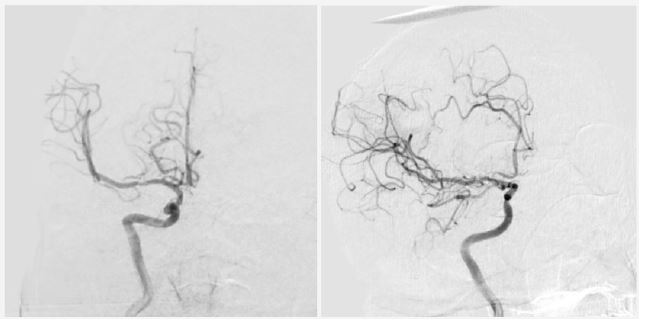

Investigations: Non-contrast CT revealed ischemic changes in the right MCA territory with an Alberta Stroke Program Early CT Score (ASPECTS) score of 6 (Figure 1). The patient was deemed ineligible for pharmacological or mechanical recanalization due to exceeding the therapeutic window.

Figure 1: Computed tomography scan upon patient admission. Evidence of ischemic stroke due to right MCA occlusion is observed.